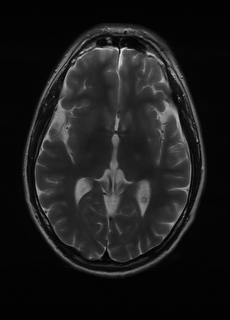

As we observe from the right image in Fig. 2, our BRM, both from MIMO and SISO settings, predicts the performance of dedicated models with a high correlation. We further choose the best three , and perform the last stage of fine-tuning accordingly to (6). A visual evaluation on real data is shown in Fig. 3. For simulated data, please refer to the Supplemental Material section.

Base on the best performing , we perceive that among , , and FLAIR, the results are best when is sampled the most. We suggest that this makes intuitive sense as images provide the best contrast out of the three sequences, which can compensate for the details lost in other images. The same observation can be made on the simulated data, where both and FLAIR show good contrast. When the time setting is changed to non-uniformity, we can see that our search for the best sampling strategy reflects the change. is sampled more as a result of faster acquisition time, while is still sufficiently sampled.

| Sequence | LR | SISO | MIMO | MIMO tuned | GT |

|---|---|---|---|---|---|

(a) 34.38/0.9371

(a) 34.38/0.9371

|

(b) 42.42/0.9883

(b) 42.42/0.9883

|

(c) 44.60/0.9920

(c) 44.60/0.9920

|

(d) 45.50/0.9940

(d) 45.50/0.9940

|

(e) PSNR/SSIM

(e) PSNR/SSIM

|

|

(f) 29.74/0.8903

(f) 29.74/0.8903

|

(g) 36.25/0.9734

(g) 36.25/0.9734

|

(h) 36.42/0.9752

(h) 36.42/0.9752

|

(i) 37.70/0.9832

(i) 37.70/0.9832

|

(j) PSNR/SSIM

(j) PSNR/SSIM

|

|

(k) 39.89/0.9311

(k) 39.89/0.9311

|

(l) 43.94/0.9864

(l) 43.94/0.9864

|

(m) 44.74/0.9883

(m) 44.74/0.9883

|

(n) 45.49/0.9894

(n) 45.49/0.9894

|

(o) PSNR/SSIM

(o) PSNR/SSIM

|